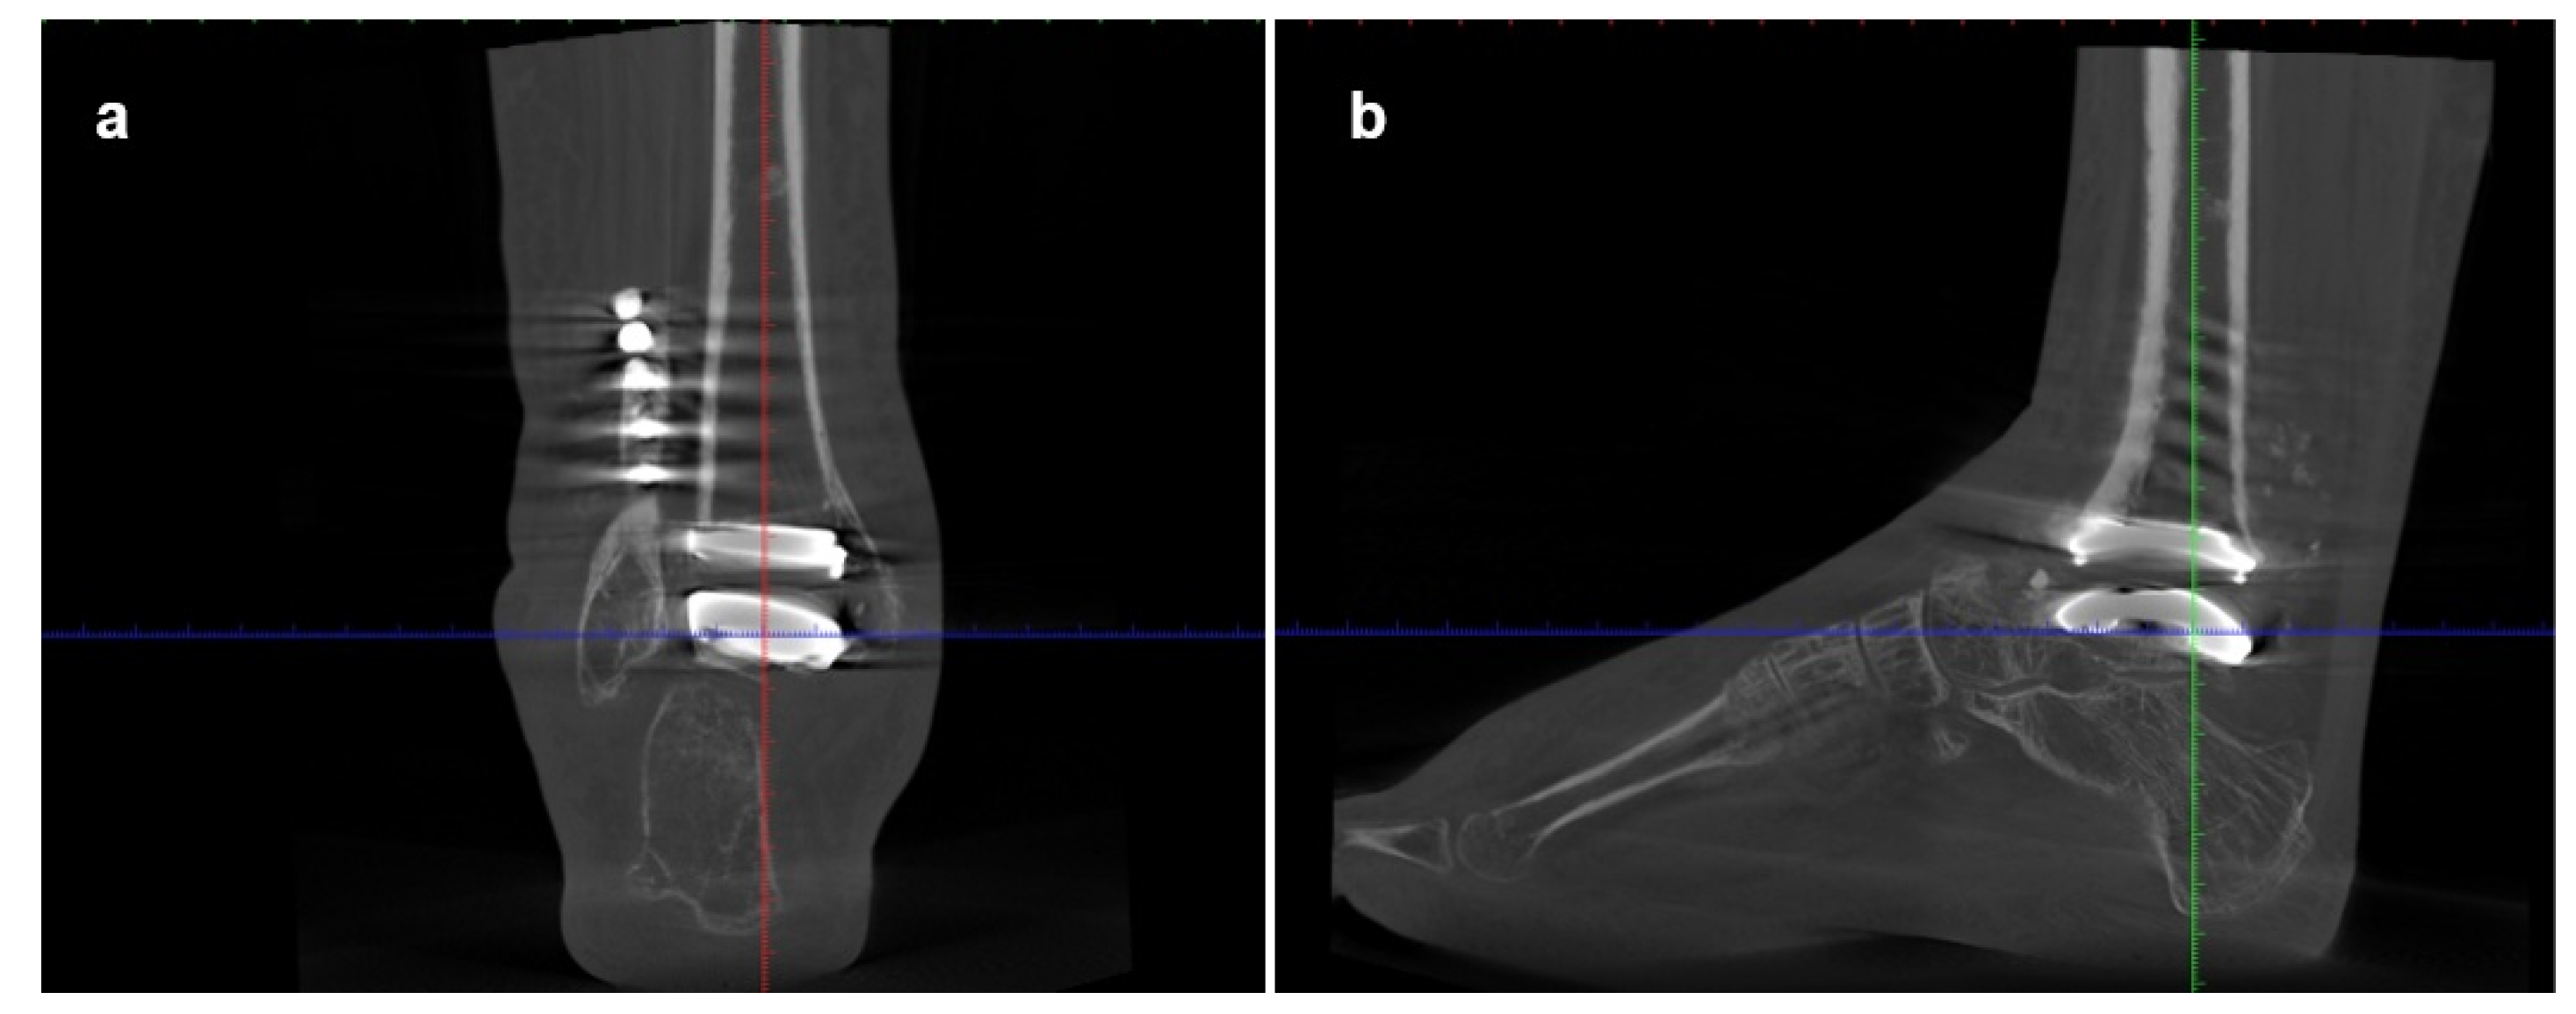

Imaging assessment included conventional bilateral foot and ankle weight-bearing radiographs in anteroposterior, lateral, and Saltzman views (Figure 1), as well as bilateral Weight-Bearing CT (WBCT) scans (Figure 2). Imaging demonstrated advanced right ankle osteoarthritis (Kellgren–Lawrence grade 4[8]) with severe distal tibial bone deformity.

Hindfoot and ankle alignment were fixed in varus and equinus, with an anterior shift of the talus relative to the tibia. Radiographic measurements, are summarized in Table 1.

Figure 1. Preoperative weight-bearing radiographs of Case one: a) anteroposterior view; b) lateral view; c) Saltzman view.